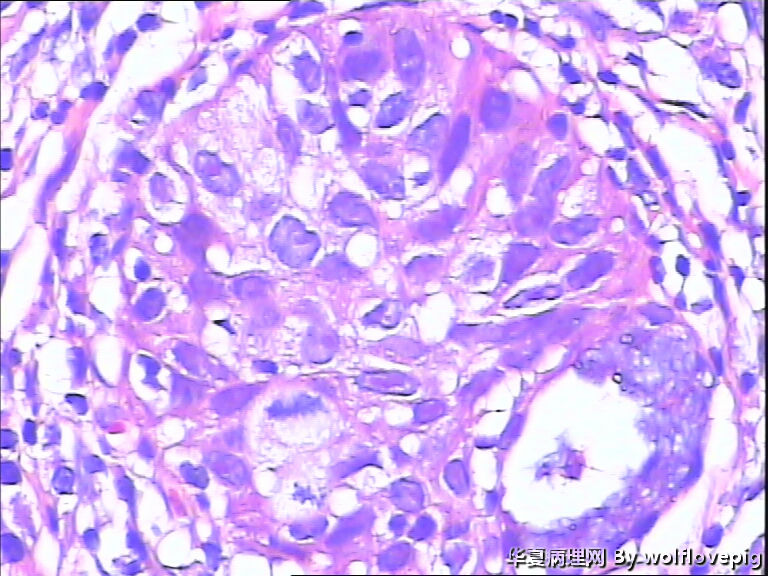

求助,宫颈!

37y

CIN3累腺

CINIII累及腺体

同意CINIII累及腺体

CIN-II 累及腺体。我看不够原位癌。学习了!

CIN2-3,累腺